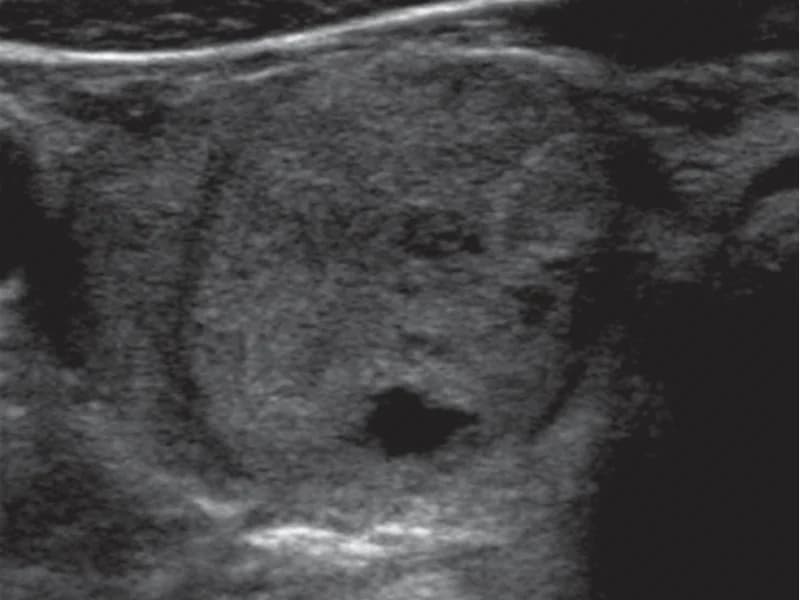

Nódulos em pacientes com Hashimoto

Tireoidite de Hashimoto pode causar pseudonódulos:

- Áreas de inflamação que parecem nódulos

- Geralmente múltiplos e mal definidos

- TI-RADS ajuda a diferenciar